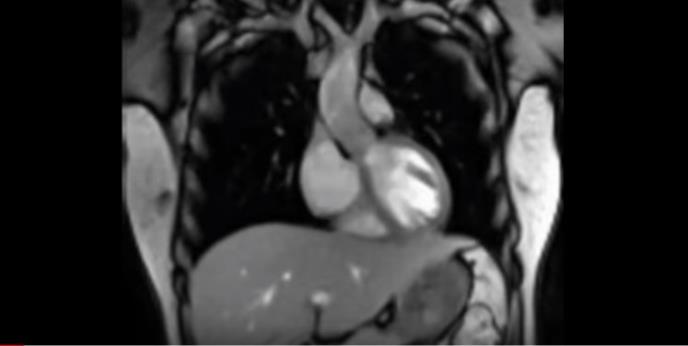

SNIMAK KOJI ĆE VAS IZNENADITI: Evo kako iznutra izgleda srce dok kuca? (VIDEO)

Naučnici nemačkog Instituta Maks Plank snimili su, pomoću magnetne rezonance, nekoliko snimaka koji prvi put prikazuju kako određeni biološki procesi izgledaju kada se gledaju "iznutra".

Na kanalu Instituta na Jutjubu postavljena su tri snimka - govora, pevanja i rada srca. Nastali su zahvaljujući novoj tehnologiji magnetne rezonance koja stvara pokretne slike u realnom vremenu.

Jedan od pionira magnetne rezonance Jens Fram, profesor nemačkog Instituta za biofizičku hemiju Maks Plank, razvio je sistem FLASH2 - koji koristi matematičke procese za rekonstrukciju skenova u pokretne slike, piše britanski Dejli mejl.

Ta tehnika je još znatno ubrzala MRI skeniranje i omogućila prikazivanje do 100 sličica u sekundi, navode iz Instituta.

"Prvi put je moguće posmatrati zajedničke pokrete, govorna kretanja, procese gutanja ili otkucaje srca onda kada se i odvijaju i izvući zaključke o tome zašto koleno boli kada se savija...", objašnjavaju naučnici.

"Sad možemo da vizealizujemo procese koje dosada nismo videli", zaključio je profesor Fram./Foto Print